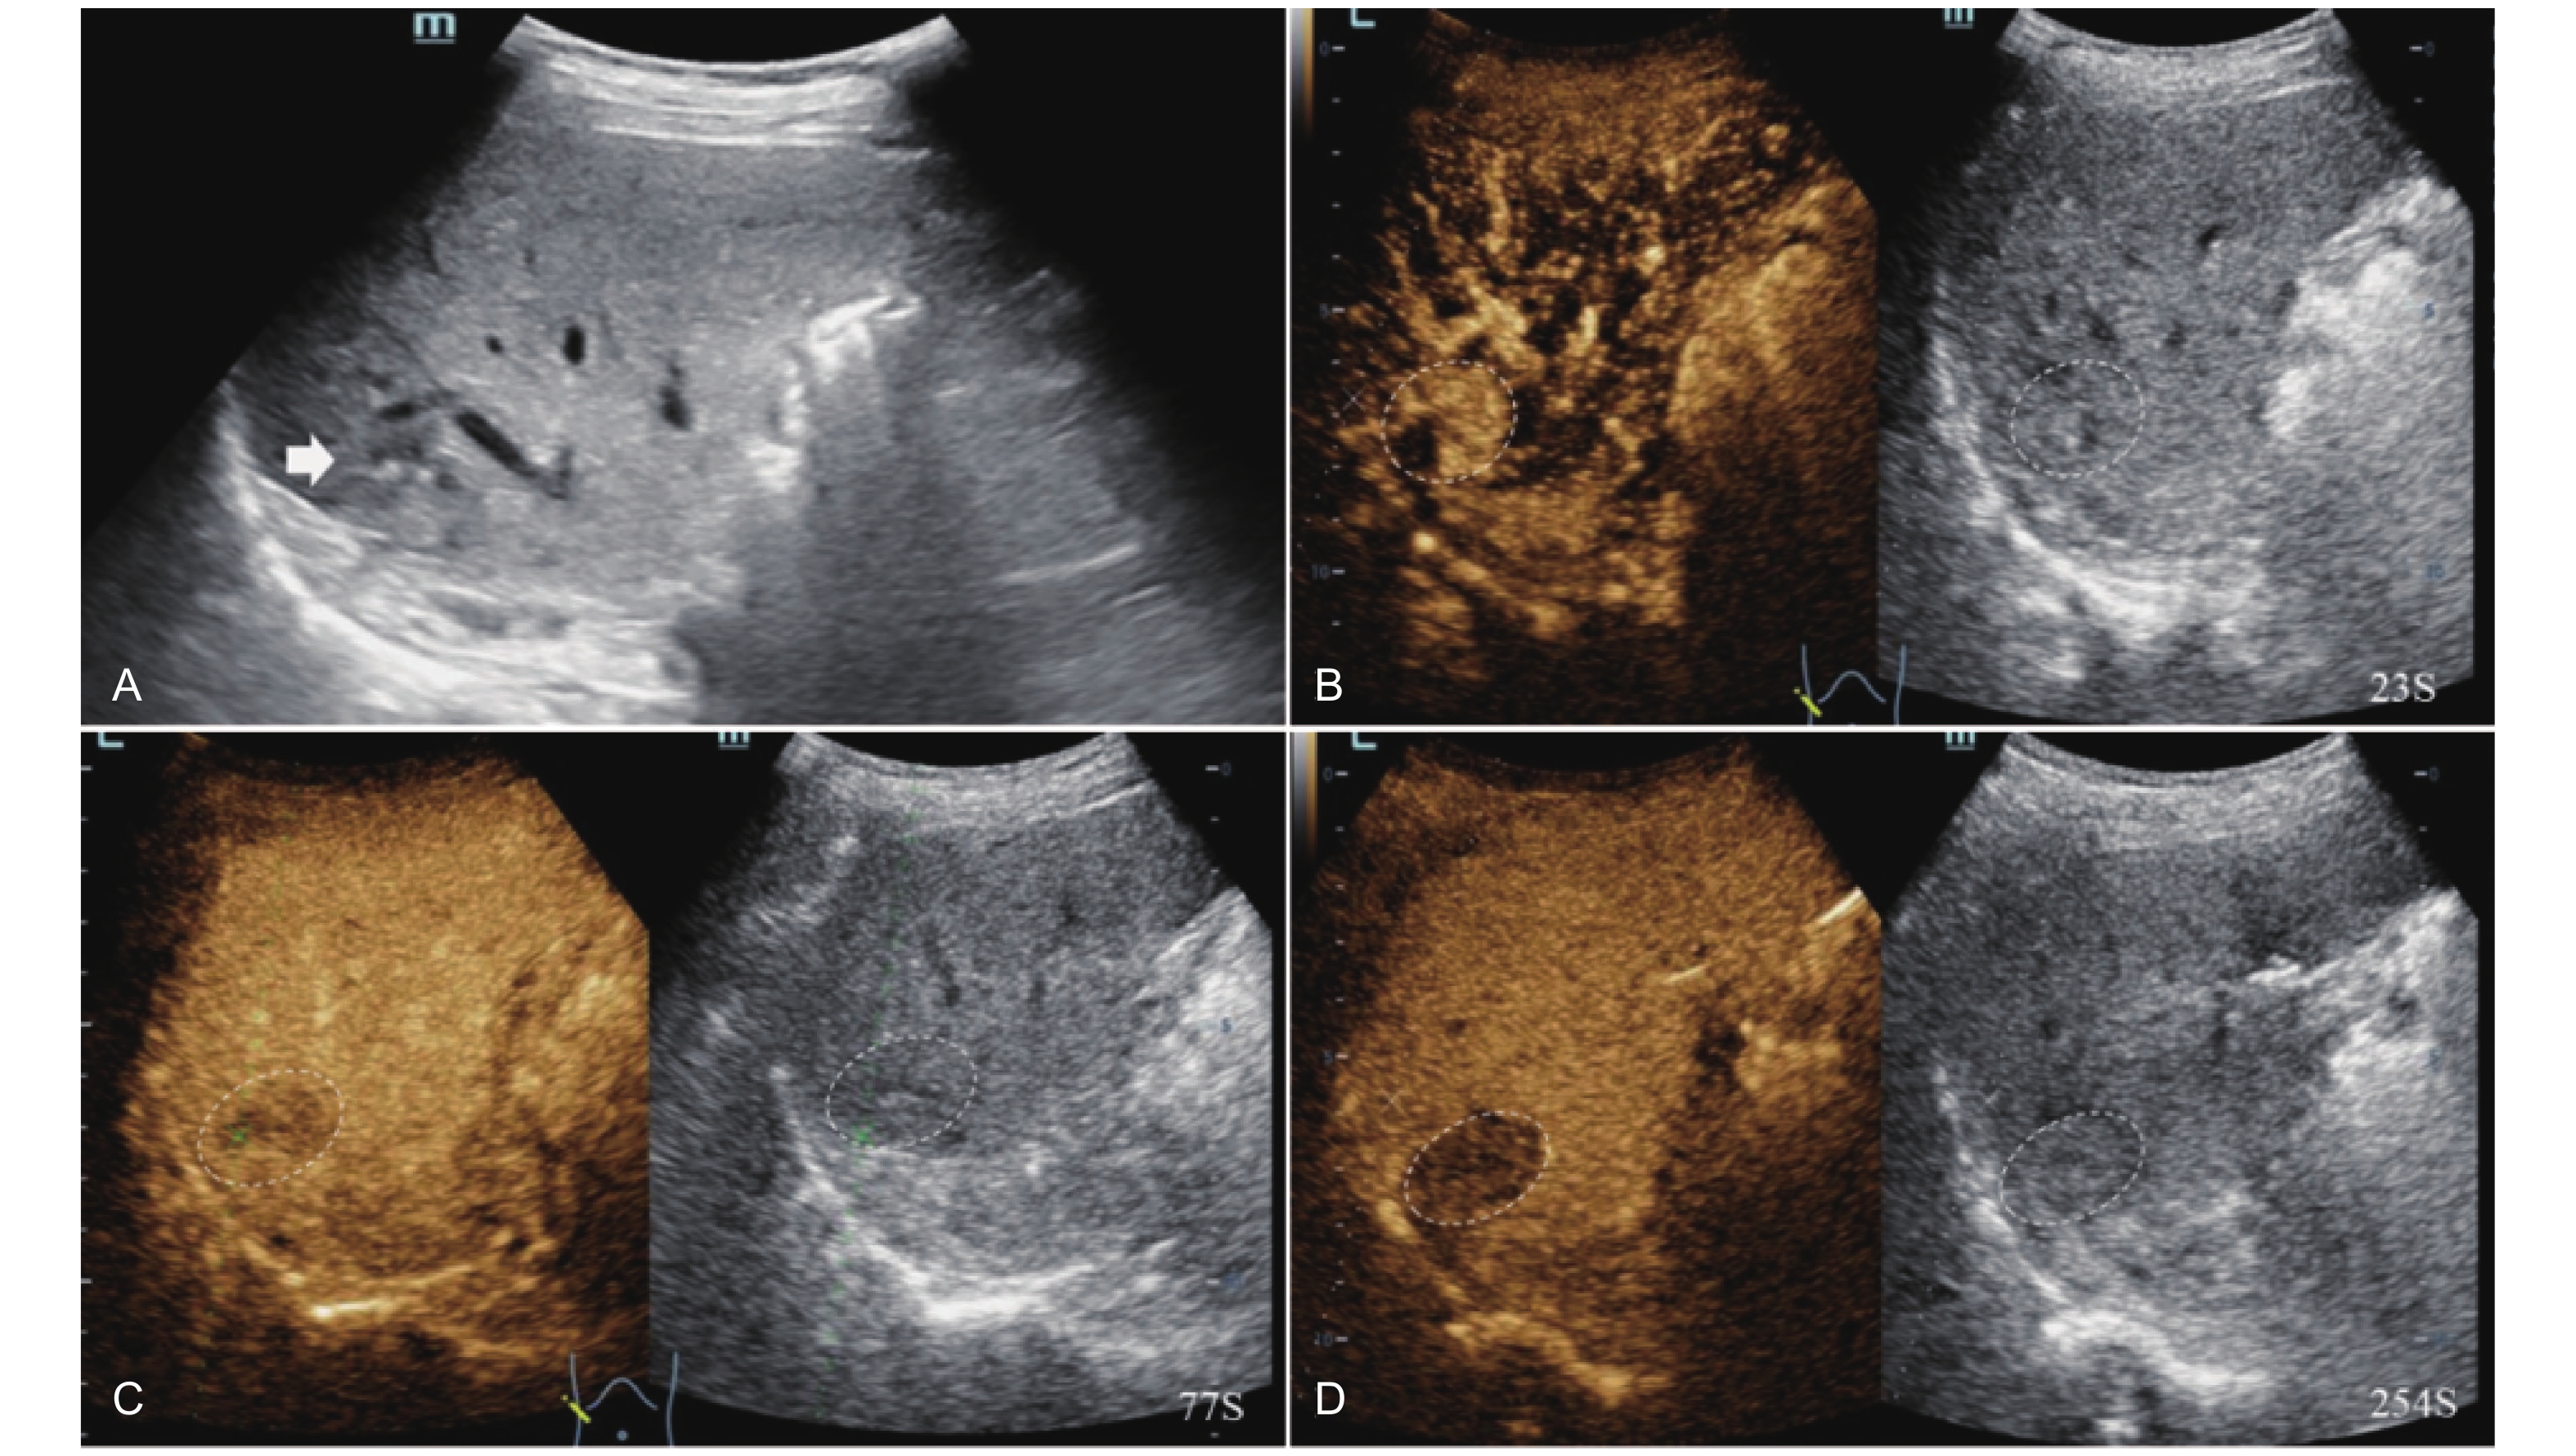

Figure 16

LR-TR Viable. Example of a treated tumor 15 days after TACE. (A) B-mode image shows slightly hyperechoic lesion with well-defined margins (thick arrow), measuring 22 mm in segment IV; (B-D) CEUS shows perilesional hyperenhancement (thin arrow) during the arterial and portal venous phases; (E) The lesion shows perilesional marked washout (thin arrow) in the late phase. No intralesional enhancement throughout all phases. Findings are consistent with LR-TR Viable."